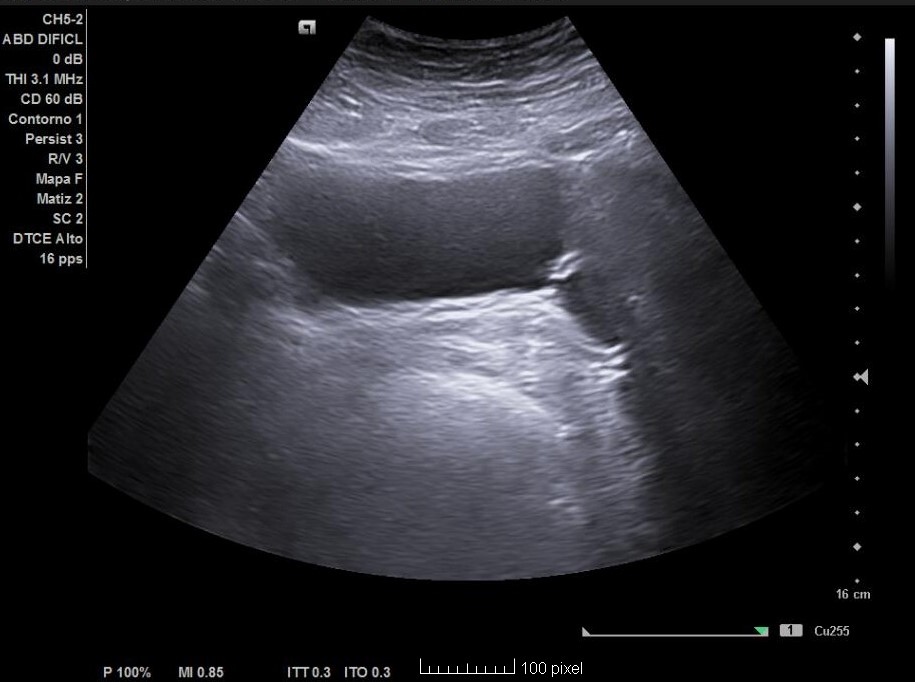

Hallazgos ecográficos

Esteatosis hepática grado I-II y además un divertículo vesical a nivel posterolateral izquierdo de 20 x 20 mm. Próstata de 22,6 cc, residuo posmiccional de 5,5 cc